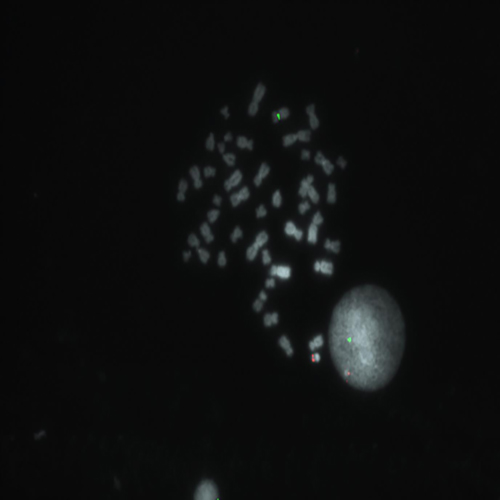

Hybridization of SE X / SE Y probe to a male metaphase spread showing normal pattern (1R1G).

Chromosomal abnormalities involving the X and Y chromosome (sex chromosomes) are slightly less common than autosomal abnormalities and are usually much less severe in their effects. The high frequency of people with sex chromosome aberrations is partly due to the fact that they are rarely lethal conditions. - Turner syndrome occurs when females inherit only one X chromosome - their genotype is X0. - Metafemales or triple-X females, inherit three X chromosomes - their genotype is XXX or more rarely XXXX or XXXXX. - Klinefelter syndrome males inherit one or more extra X chromosomes - their genotype is XXY or more rarely XXXY, XXXXY, or XY/XXY mosaic.